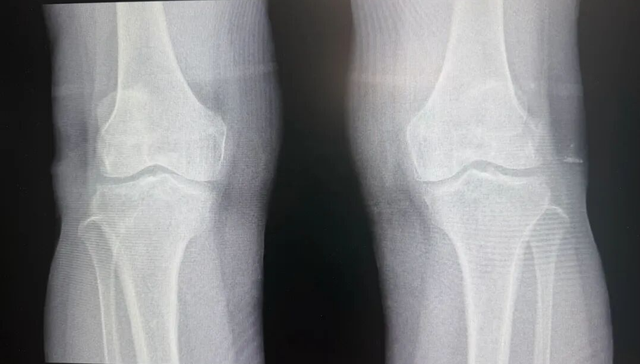

手术前: